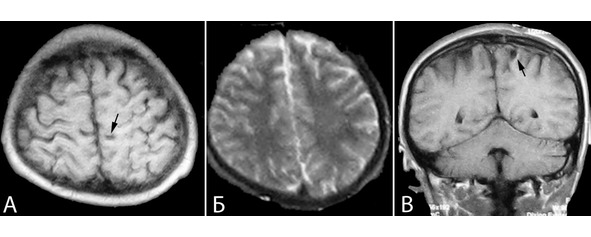

Начало заболевания за 2 месяца до госпитализации в виде тонических судорог в правой ноге. В течение последующих двух месяцев около 20 подобных приступов. Противосудорожной терапии не получал. При ЭЭГ выявлена диффузная эпилептоидная активность с акцентом слева. При МРТ выявлена кавернома в области центральных извилин слева с признаками кровоизлияния (рисунок 27).

Рисунок 27. Клиническое наблюдение №4, МРТ больного Д с каверномой в области центральных извилин слева. А – Т2 режим аксиальная проекция, Б – Т1 режим сагиттальная проекция, В – Т1 режим фронтальная проекция.

Больному выполнено удаление каверномы области постцентральной извилины слева. Во время операции при прямой стимуляции коры выявлены зоны «ноги» и «руки». Доступ согласован с полученными данными. Выполнена частичная резекция измененного кровоизлияниями мозгового вещества: резекция зоны глиотической трансформации вблизи от зоны ноги не проводилась (рисунок 28).